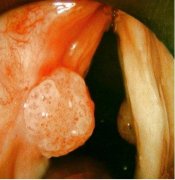

细菌性阴道炎会引起患者阴道内的分泌增多,白带有鱼腥臭味并发黄,外阴瘙痒难耐,细菌性阴道炎如不及时治疗会造成女性不孕,所以提醒患者出现问题后及早到正规医院进行诊断治疗。

阴道分泌物增多还发黄